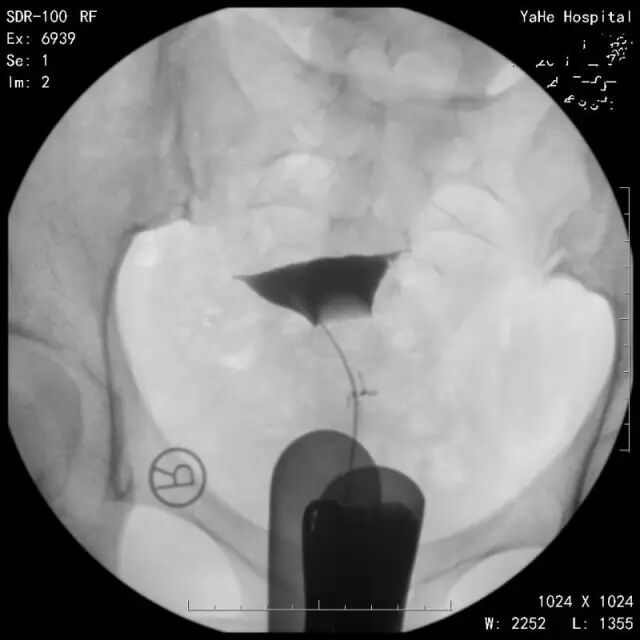

那么一张标准合格的碘水造影片长什么样呢?一起来看一组图片吧。

↑第一张:清楚地显示正常的宫腔形态。

↑第二张:显示有碘水充盈双侧输卵管腔。

↑第三张:可见碘水自伞端流出。

↑第四张:延迟涂抹片,可见碘水在盆腔内均匀涂抹。(这张非常重要,如果做了造影却没有延迟涂抹片,造影可以说白做了,无法正确做出诊断,基本靠猜,你没看错,靠猜!)